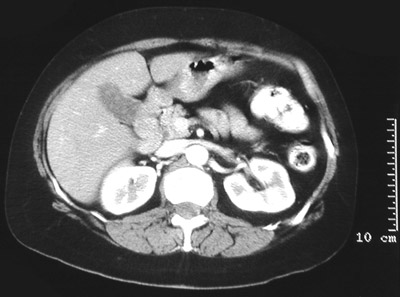

![]() | In the abdominal CT scan view above, there is an irregular mass within the lower portion of the gallbladder, with the inferior tip of the right lobe of liver adjacent to it. This mass proved to be an adenocarcinoma of the gallbladder. In the frame below, the gallbladder can be seen next to the liver. The gallbladder wall is irregular, and there are also scattered densities within the lumen, representing gallstones (up to 90% of gallbladder adenocarcinomas arise in association with gallstones). |